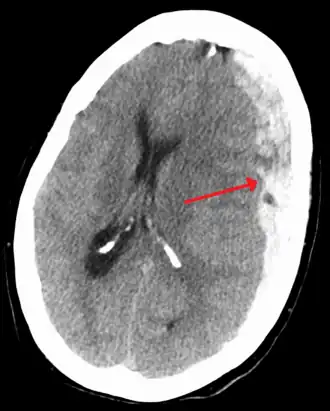

A person must receive medical assessment, including a complete neurological examination, after any head trauma. A CT scan or MRI scan will usually detect significant subdural hematomas.

Subdural hematomas occur most often around the tops and sides of the frontal and parietal lobes.[3][2] They also occur in the posterior cranial fossa, and near the falx cerebri and tentorium cerebelli.[3] Unlike epidural hematomas, which cannot expand past the sutures of the skull, subdural hematomas can expand along the inside of the skull, creating a concave shape that follows the curve of the brain, stopping only at dural reflections like the tentorium cerebelli and falx cerebri.

On a CT scan, subdural hematomas are classically crescent-shaped, with a concave surface away from the skull. However, they can have a convex appearance, especially in the early stages of bleeding. This may cause difficulty in distinguishing between subdural and epidural hemorrhages. A more reliable indicator of subdural hemorrhage is its involvement of a larger portion of the cerebral hemisphere. Subdural blood can also be seen as a layering density along the tentorium cerebelli. This can be a chronic, stable process, since the feeding system is low-pressure. In such cases, subtle signs of bleeding—such as effacement of sulci or medial displacement of the junction between gray matter and white matter—may be apparent.

Fresh subdural bleeding is hyperdense, but becomes more hypodense over time due to dissolution of cellular elements. After 3–14 days, the bleeding becomes isodense with brain tissue and may therefore be missed.[20] Subsequently, it will become more hypodense than brain tissue.[21]